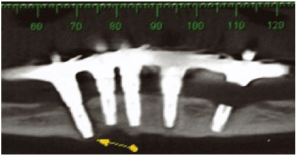

访问期间,增加成交量中观察到的后区右侧下颌骨和流动性在该地区的最末端的植入物,它是不可能的诊断是否产生的流动性被植入或下颌骨折(图1)。图像检查后,在皮瓣嵴处观察到一条透光线,一直延伸到种植体基底处,这表明下颌骨骨折无碎片脱离。我们还可以观察到,这是一个骨高度小的下颌骨,除了一个外,其他种植体显示边缘骨丢失(图2和3)。

图2:在下颌骨左侧和右侧远端种植体周围的ct切面可以观察到种植体骨折,提示下颌骨骨折。